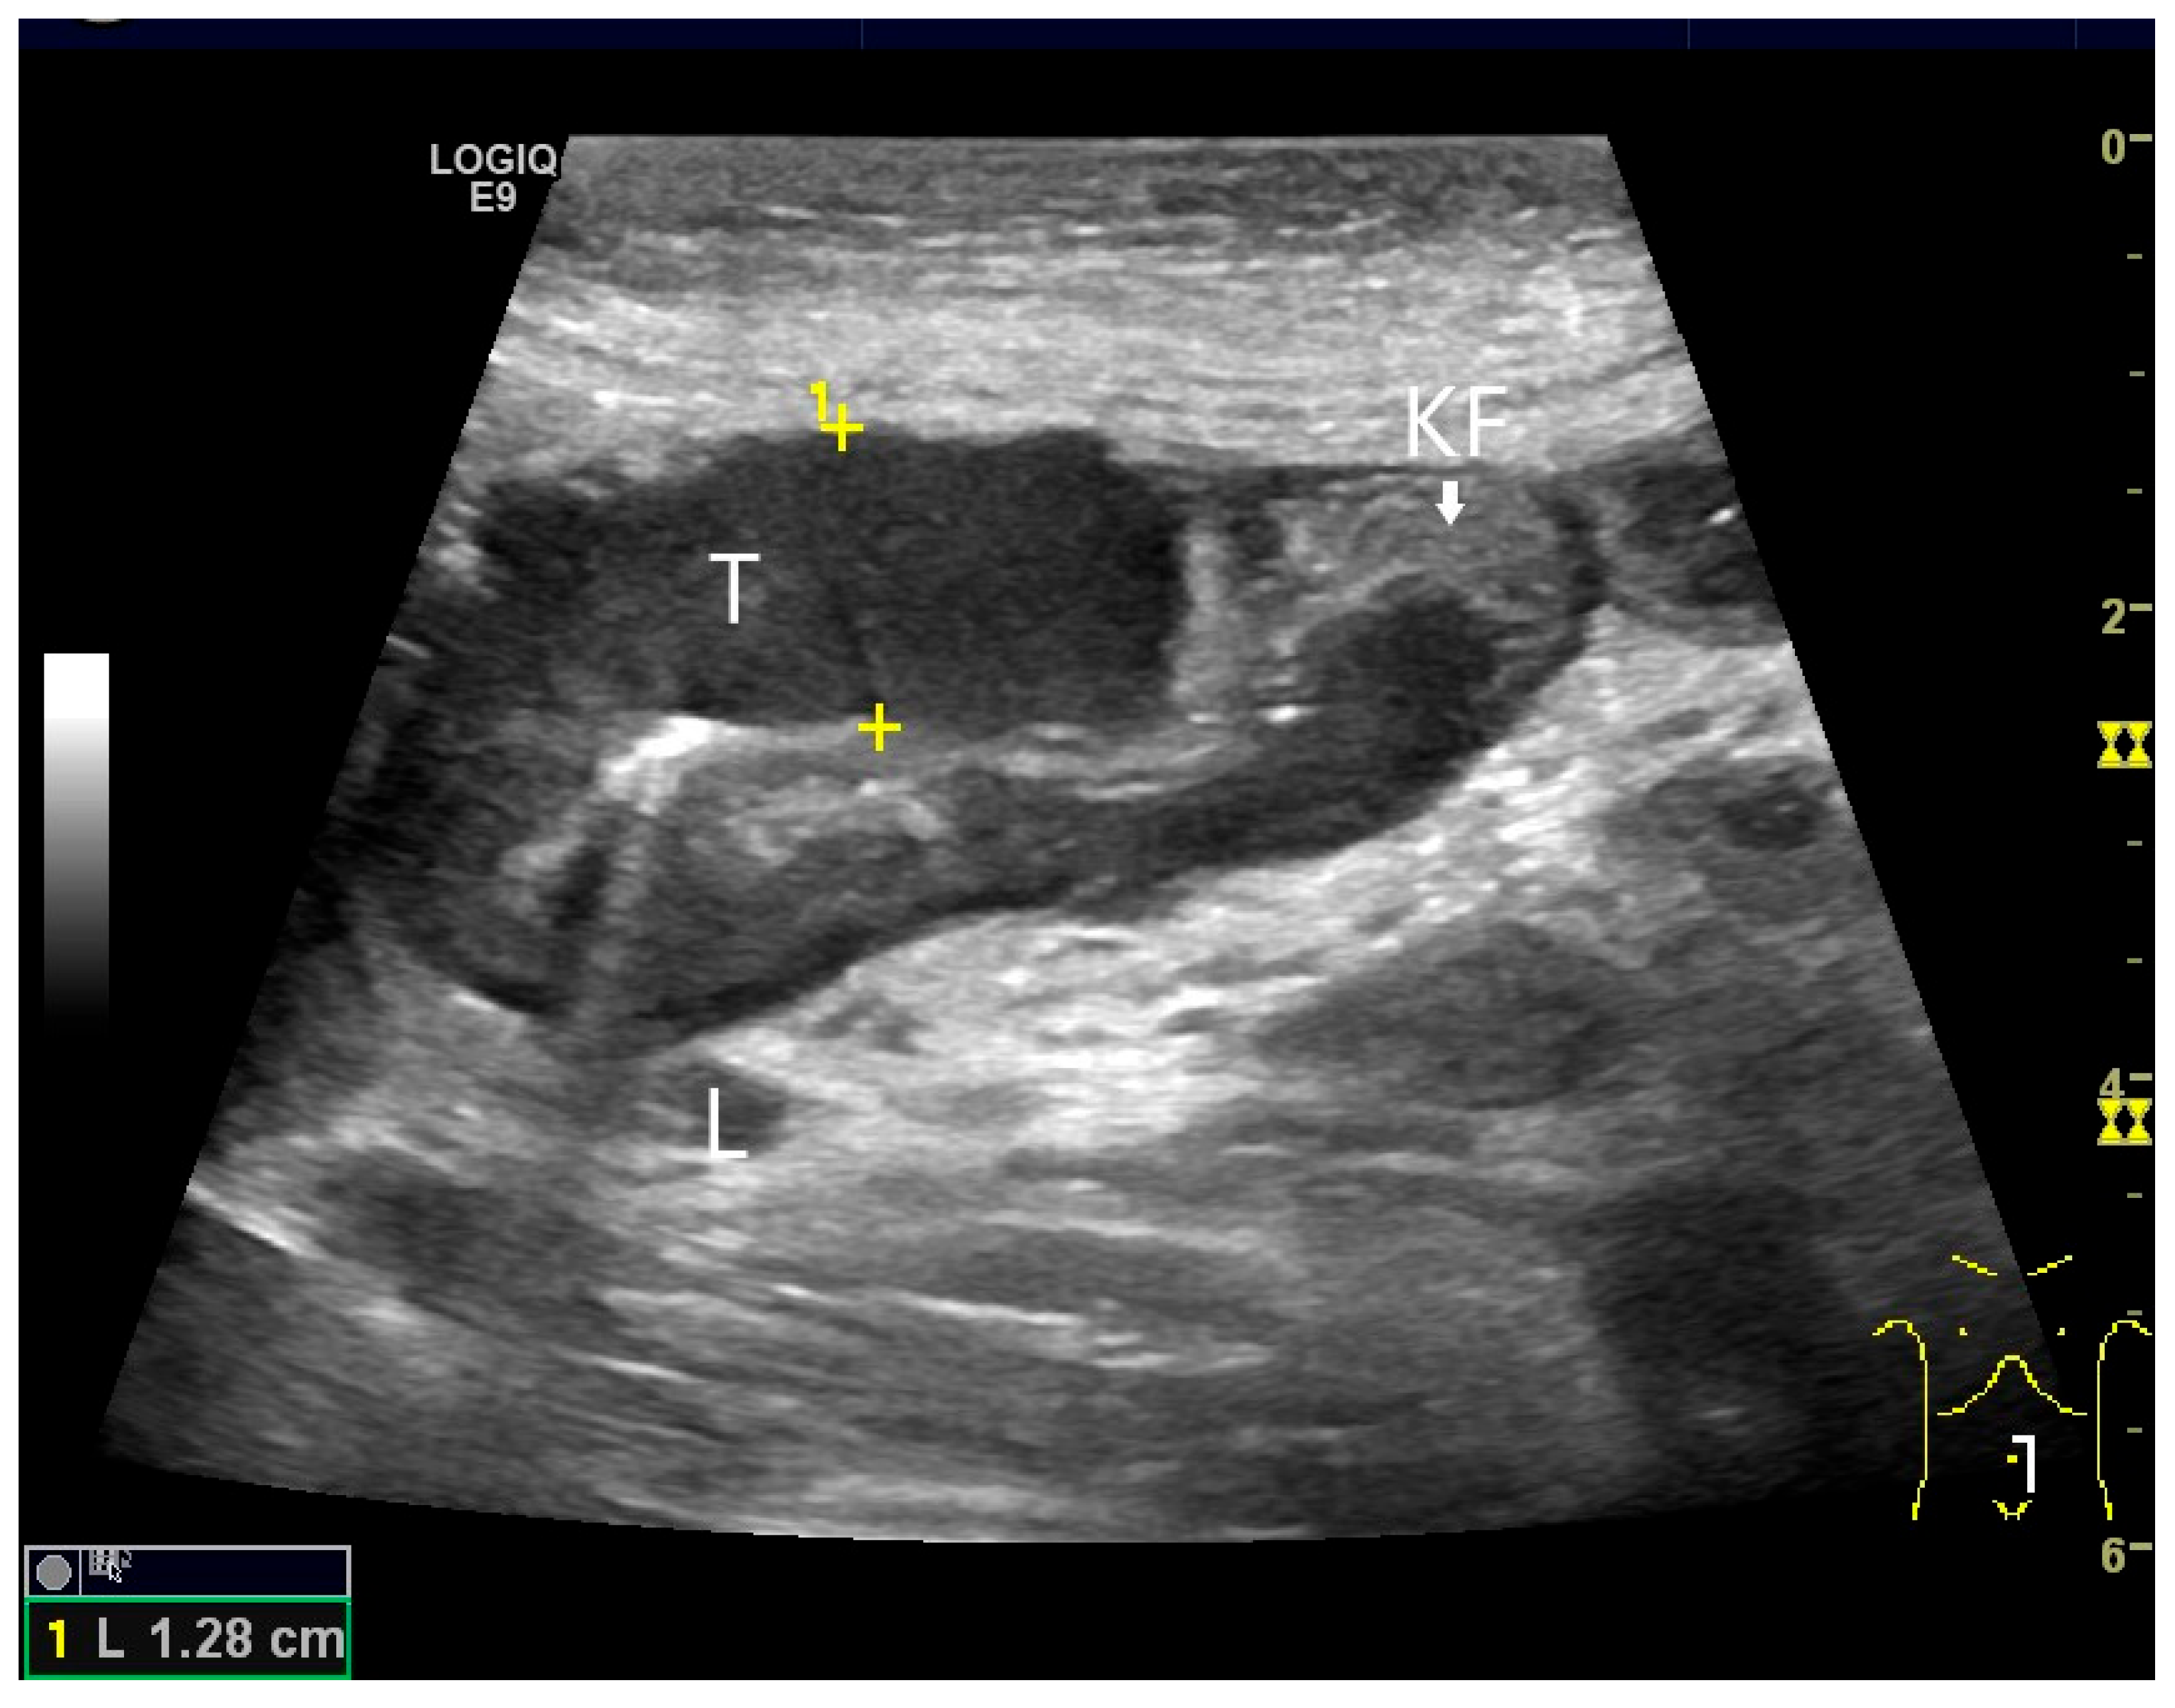

- Rispo, A.; De Sire, R.; D’Armiento, M.; De Bonis, L.; Tropeano, F.P.; Ricciolino, S.; Nardone, G.; Luglio, G. Ultrasonographic diagnosis of ileo-ileal intussusception secondary to Vanek’s tumor. Eur. Rev. Med. Pharmacol. Sci. 2022, 26, 350–353. [Google Scholar] [CrossRef]

| GIST | Round hypoechoic masses, homogeneous or heterogeneous depending on size. They usually originate from the muscularis propria, which can be difficult to distinguish in US. Small vessels on CDI, hyperenhancement on CEUS. They move with the small intestine and can change position. |

| Intussusception | The small intestine proximal to the tumor is invaginated. More than five wall layers are seen in an onion-skin shape. |